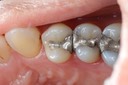

Frank Fukuda #30 pre-op